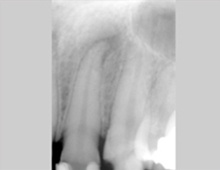

Bei der Wurzelbehandlung wird der Zahn unter örtlicher Behandlung aufgebohrt und der erkrankte oder abgestorbene Zahnnerv entfernt. Anschließend wird der Wurzelkanal gereinigt, desinfiziert und mit einer Wurzelfüllung versorgt. Das Pulpa-Füllmaterial zeichnet sich durch höchste Gewebefreundlichkeit und Volumenstabilität aus.

Eine Wurzelbehandlung erfordert höchstes zahnärztliches Können und Fingerspitzengefühl. So ist das Auffinden und Aufbereiten der teilweise sehr engen, gekrümmten Wurzelkanäle schwierig und erfordert einen längeren Behandlungsaufwand. Wir verwenden modernste und flexible Instrumente, sie sorgen für eine sichere und effiziente Wurzekanalaufbereitung.